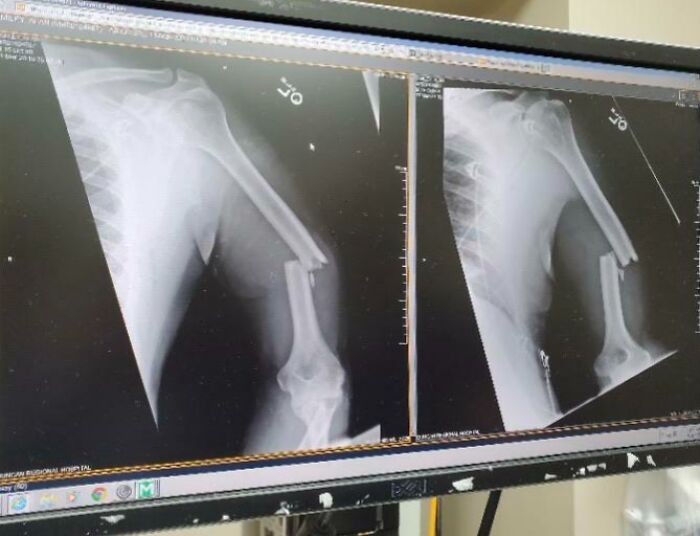

My (Nearly 60 Y/O) Fathers Arm After Being Thwomped By A Cow This Morning